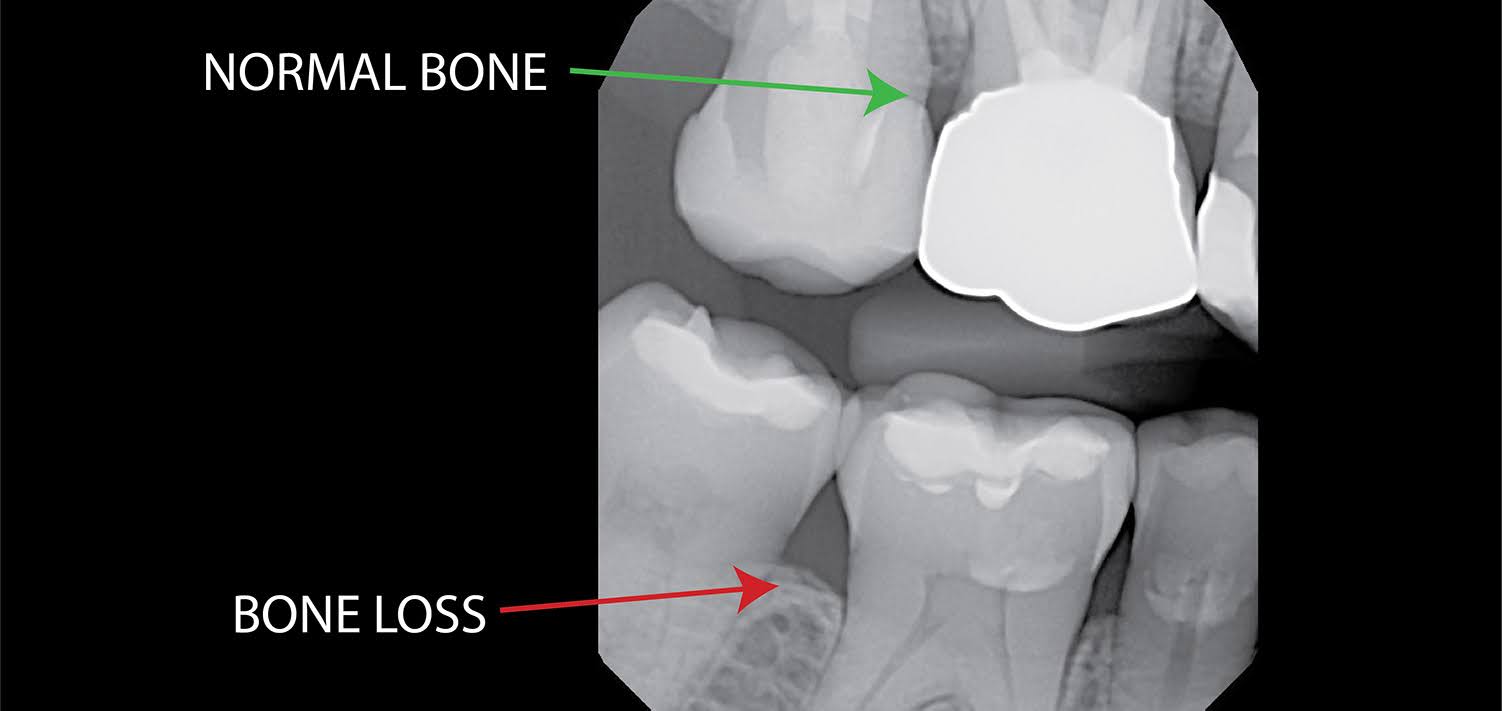

5. Bone Loss in the Jaw

Bone loss can occur due to untreated gum disease or long-term missing teeth. When there isn’t enough bone to support the tooth, it may begin to loosen.

This process is often gradual but can become severe over time.

Signs:

- Changes in bite

- Gum recession

- Tooth movement

Treatment:

- Bone grafting

- Periodontal treatment

- Tooth replacement options